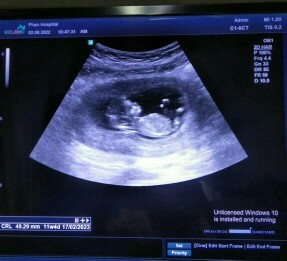

ซาวตอน11วีค3วันค่ะ น้องโตกว่าเกณฑ์ไป3วัน 5.6cmค่ะ ❤️

รูปซาวดฺ์ตอน11w4dค่ะ ตอนนี้13w3dแล้วค้ะ